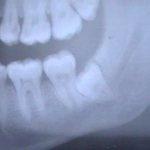

4. Общий рентген – выявляет наличие карманов у подозрительной коронки, кариес внутри корня на рентгене выглядит как затемненный участок. Чтобы диагностировать скрытый тип патологии, применяют визограф – идеальное решение для визуального рассмотрения аномалии в различных проекциях.